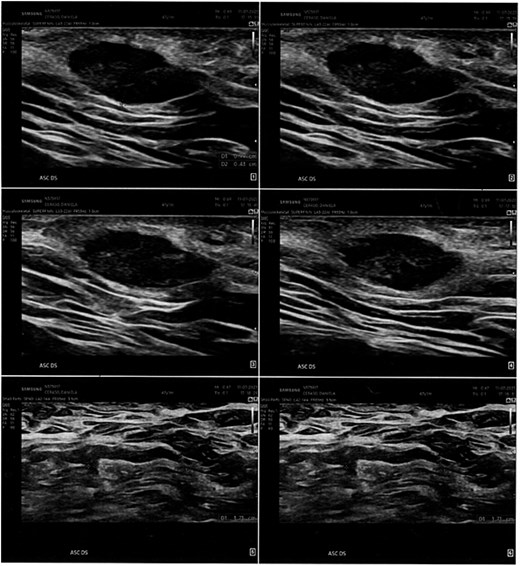

We present the case of a 48-year-old female patient with a medical history of hypothyroidism, treated with levothyroxine, and fibrocystic mastopathy, which is under ongoing follow-up. In 2021, the patient developed a subcutaneous swelling in the right axillary region. Initially, it was asymptomatic and showed no signs of inflammation. During the same year, two ultrasound scans of the axillary area were performed. Both scans revealed a hypoechoic lesion with regular borders, without signs of lymph node involvement, and the initial diagnosis was a sebaceous cyst (Figs 1 and 2).

Ultrasonographic examination performed in the right axillary cavity shows in the superficial planes a centimetric oval, hypoechogenic, regular-edged shape to be varably referred to sebaceous cyst. Loco-regional lymph nodes in the deep planes, diam max 17 mm.

The clinically appreciable formation in the right axillary site corispondes to a todouble, well-defined contour, hypoechogenic image, lacking colorimetric signal, compatible for sebaceous cyst of 3 x 2 mm diam. Absence of locoregional lymph node hyperplasia.